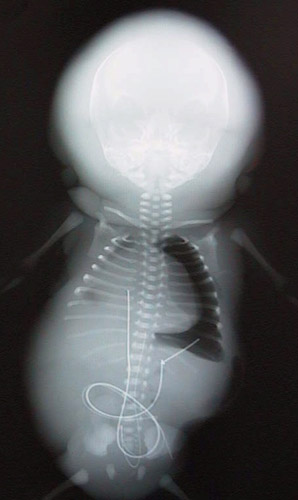

![]() | This whole body radiograph reveals marked soft tissue thickening, particularly evident around the skull, in this preterm baby with hydrops fetalis from congestive heart failure. This baby was the recipient twin of a twin-to-twin transfusion syndrome. There is also a left pneumothorax as a result of intubation and positive pressure ventilation required in resuscitation efforts because of severe pulmonary hypoplasia. An umbilical artery catheter is in place (the proximal end has been tied off). |